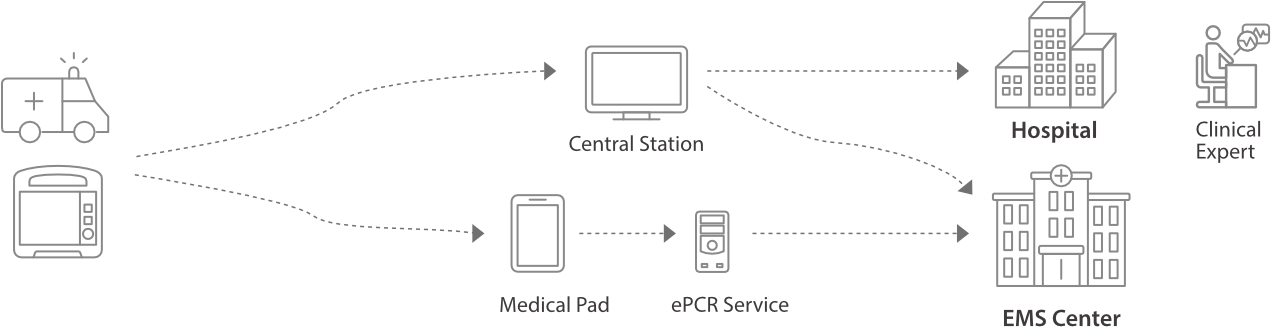

Los perfiles de configuraciÃģn se pueden personalizar y cargar fÃĄcilmente para diferentes situaciones clÃnicas o requisitos de uso, e incluyen los valores predeterminados, el dise?o de la pantalla y la configuraciÃģn del sistema.